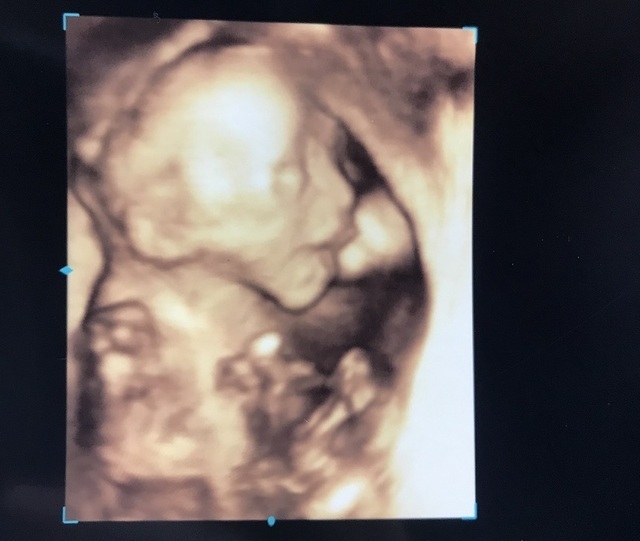

21週3日(21w3d・女の子)|うさぎいぬ さん(22歳)

エコー写真撮影時のエピソード:

エコー写真の時はいつも顔に手がかかっていて、はじめてきれいに顔が映った唯一のエコー写真です。

妊婦の時はこのエコー写真を見ながら、旦那さんと二人で目はどっち似だねーとか鼻はどっち似だねーと、いつも生まれてくる子どもの話をしていました。